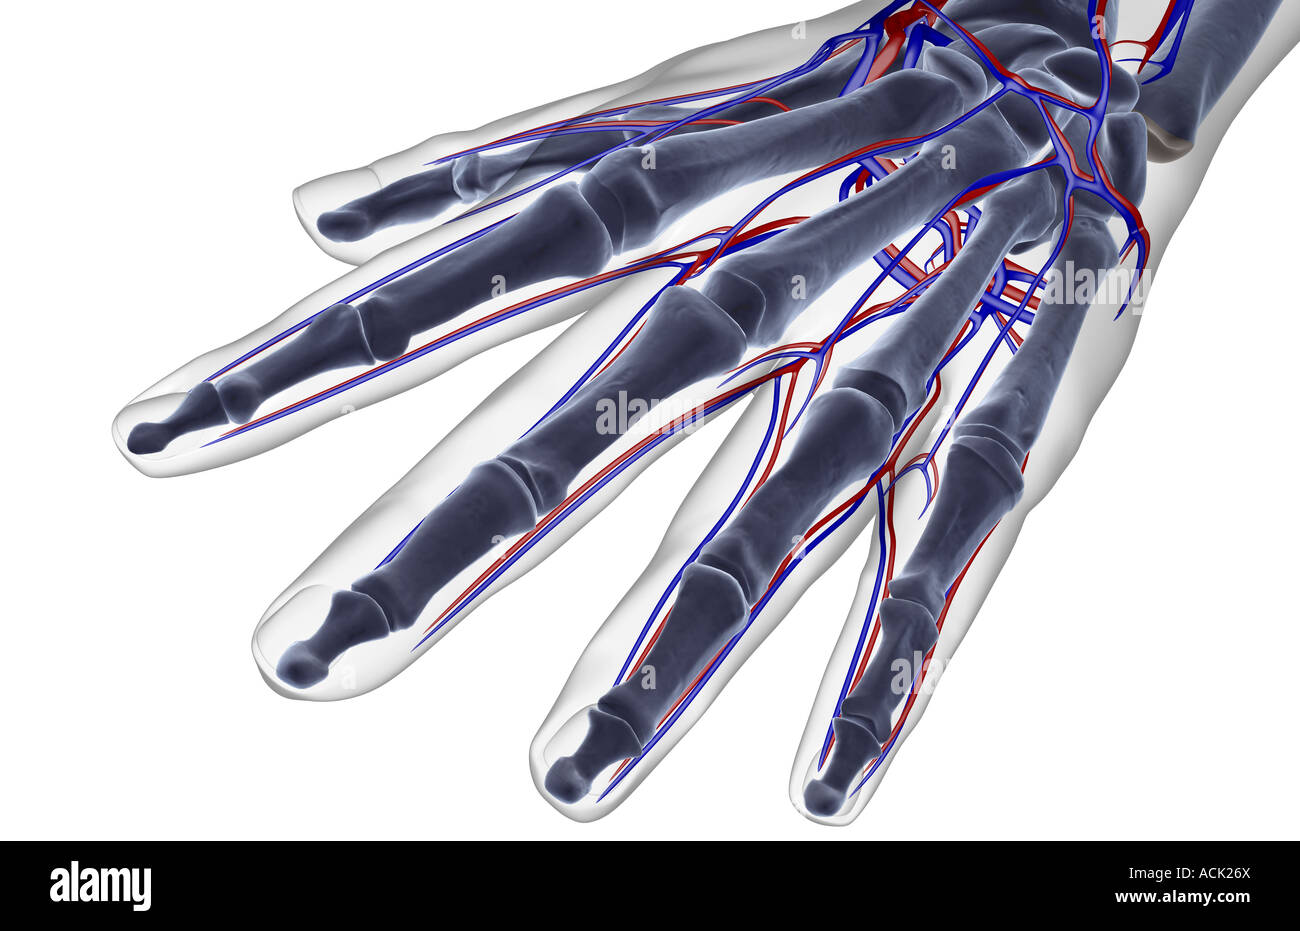

The blood supply of the hand Stock Photohttps://www.alamy.com/image-license-details/?v=1https://www.alamy.com/stock-photo-the-blood-supply-of-the-hand-13175089.html

The blood supply of the hand Stock Photohttps://www.alamy.com/image-license-details/?v=1https://www.alamy.com/stock-photo-the-blood-supply-of-the-hand-13175089.htmlRFACK26X–The blood supply of the hand